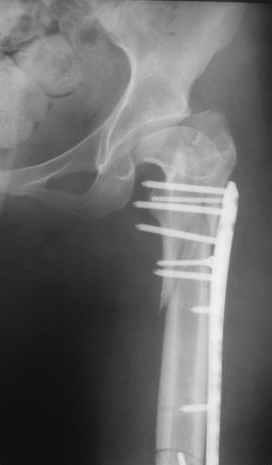

Прошу прощения, со снимками глюк произошел. Высылаю. С уважением Евгений У.

Получилось очень симпатично, мои поздравления. А можно фото конечности без наклеек посмотреть?

И межфрагментарный винт на диафизе - так ли он нужен при выбранном варианте остеосинтеза с относительной стабильностью?

Хотя все-таки закрыто антгерадно заштифтовать тут было вполне можно, и при использовании отечетственного имплантата лечение обошлось бы на порядок дешевле. Опасения коллеги Кульджанова насчет кровоснабжения головки бедра и предстоящих операции в этой области кажуься несколько

преувеличенными - и стержень можно через вертел ввести, да и расстройства кровоснабжения головки, если они случатся после штифтования, не будут длиться вечно.

Но в люом случае, что сделано - то сделано, и сделанное выглядит вполне обнадеживающе, так что еще раз поздравляю коллег с успешным выходом из непростой ситуации.